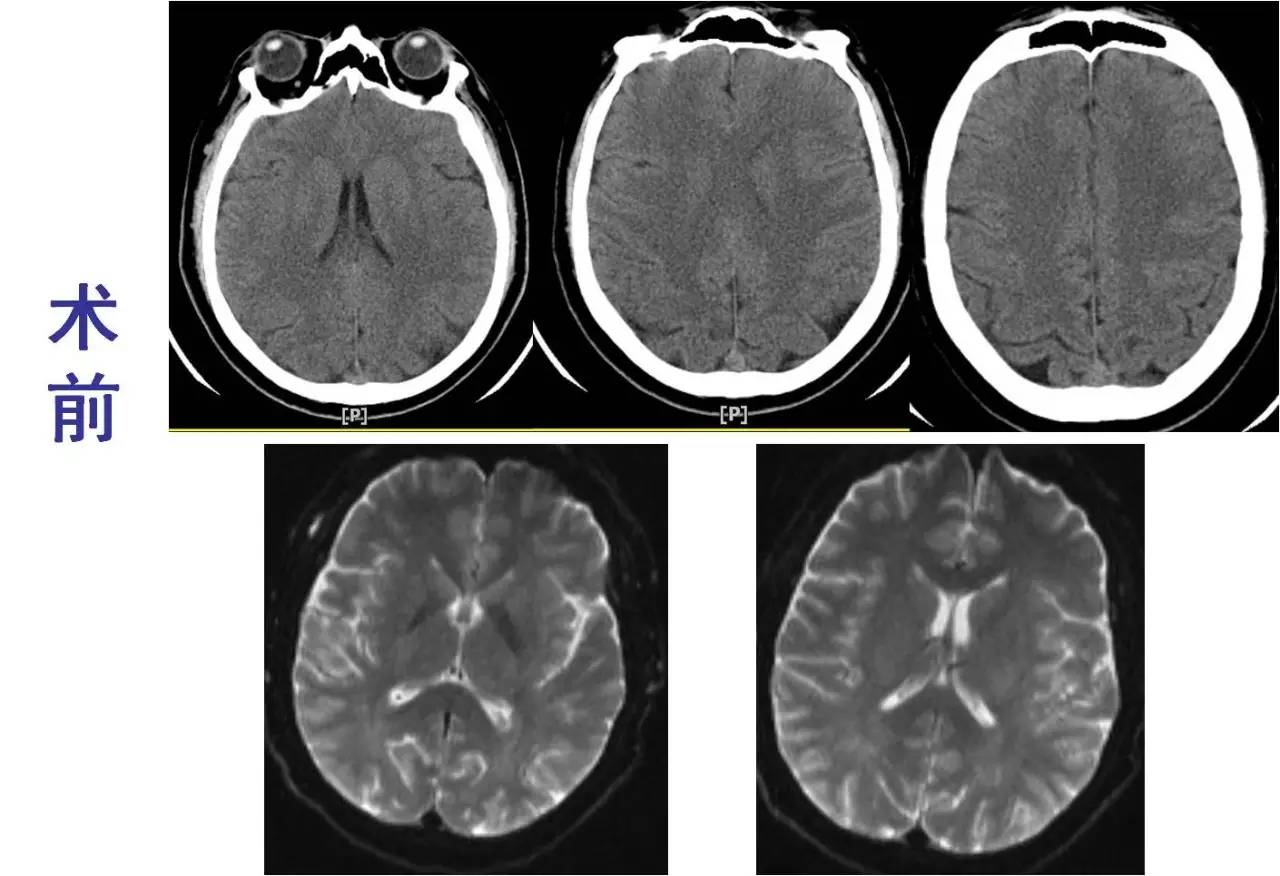

术前

术后

》意识清楚,言语流利,四肢活动自如;

》四肢肌力Ⅴ级;

》术后24小时NIHSS评分:0分;

》5天后主动脉换瓣术;

》90天mRS评分0分。